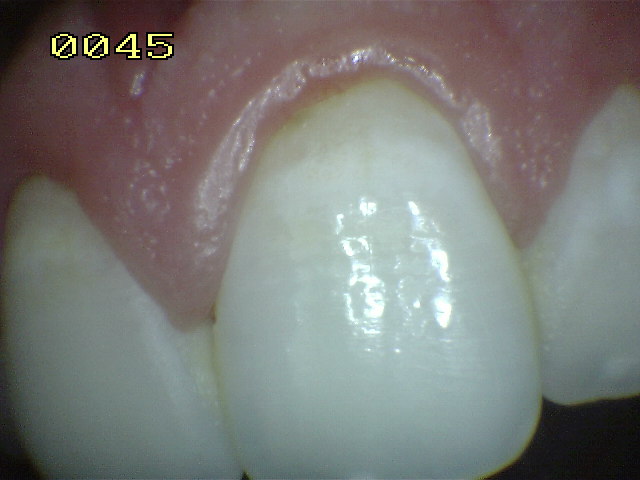

Encía Normal |